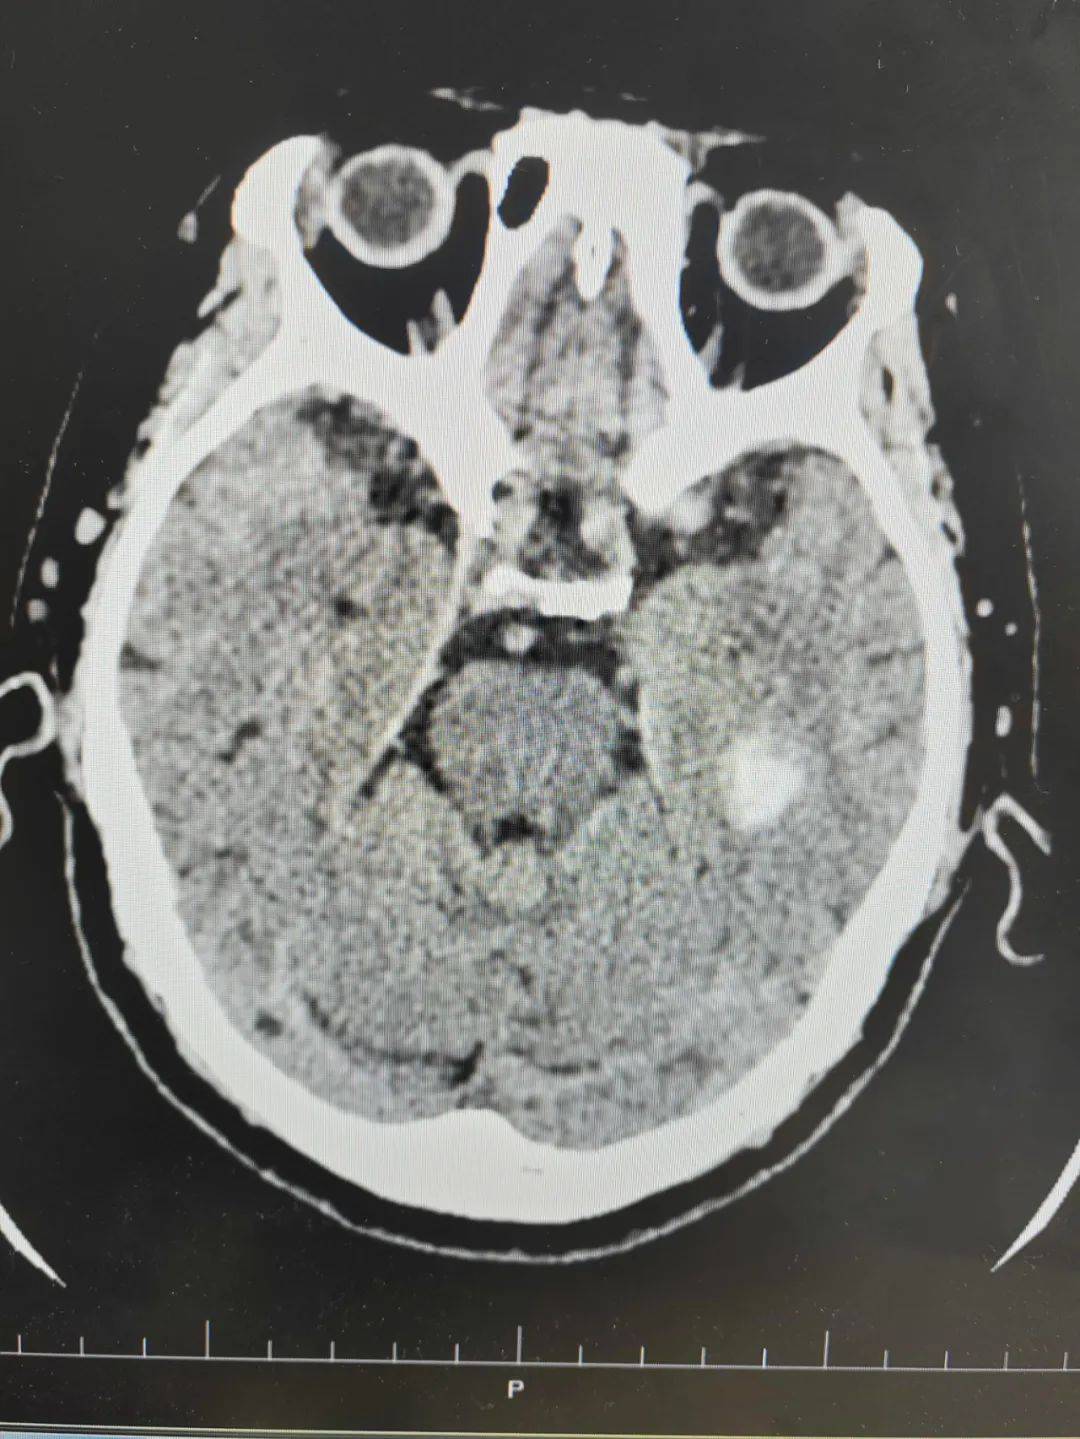

59岁男性患者,突发动脉瘤破裂出血1小时余, hunt

图片尺寸2736x3648